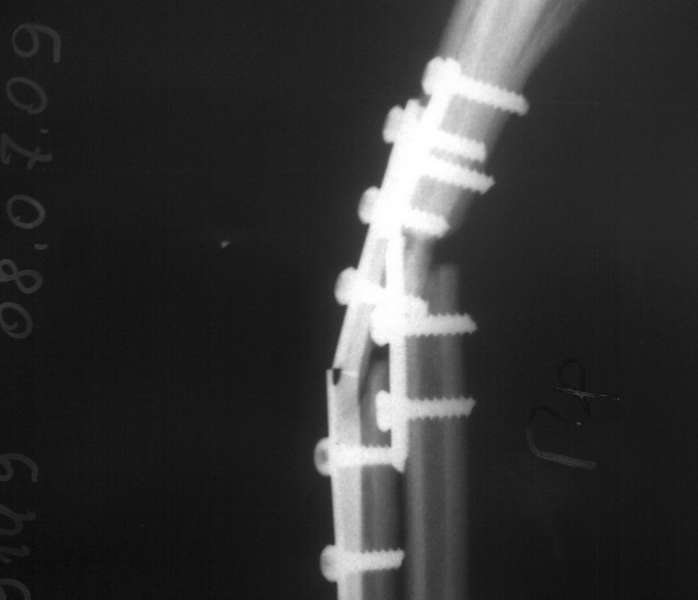

Пациентка С. 23 лет. В марте 2009 года операция остеосинтез костей предплечья пластинами по поводу оскольчатого перелома.

04.07.09. при совершении супинационных движений предплечья ощутила хруст (низкоэнергетическая травма). На рентгенограммах несросшийся перелом костей предплечья, перелом конструкций. Коллеги подскажите что делать, поделитесь опытом.

Спасибо коллеги. Выполнили ресинтез реконструкционными пластинами с костной аутопластикой кортикальными трансплантатами с декортикацией.

Кликните для загрузки файла 16072009402[1]

611KB (625938 bytes)